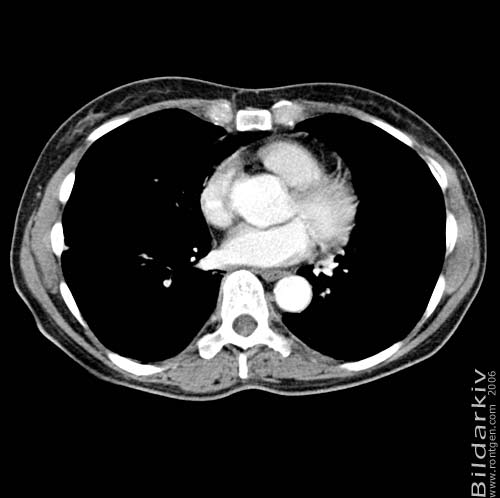

Snitt över thorax med kontrast. Sk. mediastinum-fönstersättning.

Meiastinum